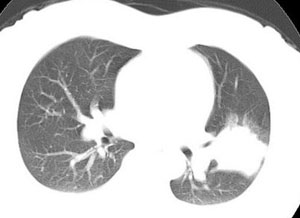

双肺野可见散在大小不等结节及肿块影,内密度不均匀,边缘部分清,部分欠清,纵隔未见明显肿大淋巴结.右侧胸腔少理积液.结合临床,考虑韦格肉芽肿可能吧,巨淋巴增生,结节病,特殊感染都要考虑.转移瘤临床不象.

多发、内可见含气支气管征,边界不清;纵隔内未内见明显肿大淋巴结。右侧少量胸腔积液。

考虑:1、化脓性肺炎?

2、肺霉菌感染?

血源性肺脓肿,内可见支气管影,不象肿瘤

两肺多发斑片及节结灶,其内有支气管充气症,比较年轻考虑为感染或肺泡癌

我考虑慢性肺炎可能性大。1、病变周边见有消淡的密度影(相对于中央密度),2、纵膈未见肿大淋巴结。3、右侧病变内仍可见清晰气管影。

两肺散在分布大小不等的肿块及结节影,边缘毛糙,有分叶、毛刺,病灶密度不均匀,可见支气管充气相与空泡征。病变大多位于胸膜下,可见胸膜凹陷及胸腔积液。气管腔静脉间可见小结节影。

病人临床仅为胸痛,暂不考虑感染性病变。

考虑多发结节型细支气管肺泡癌。